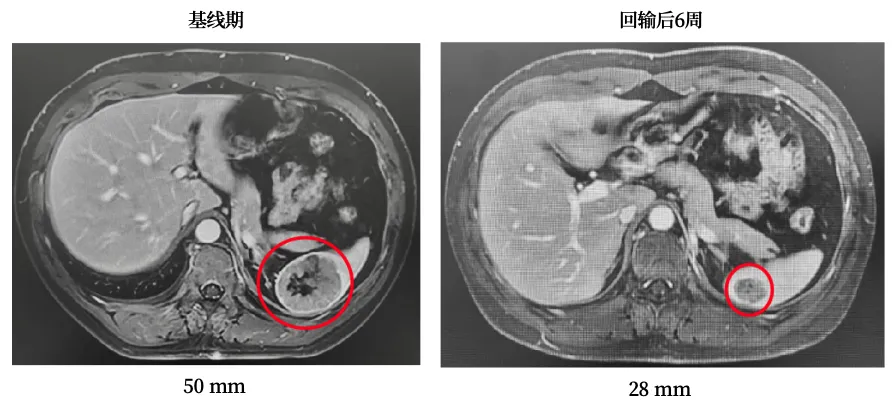

就在走投无路时,L女士参加了GC101 TIL治疗复发/晚期妇科肿瘤的临床试验,2021年8月顺利接受了单次TIL细胞回输。

受试者接受TIL回输前、回输后6周及回输后12周影像资料

出院后,每次随访结果都带来惊喜:肿瘤标志物持续降低,肿瘤不断缩小,治疗后两个多月,各项检查指标均恢复正常。如今,4年过去,L女士早已回归正常生活和工作,无需长期服药,也不用再频繁辗转于各大医院,彻底摆脱了癌症带来的生理和心理煎熬。